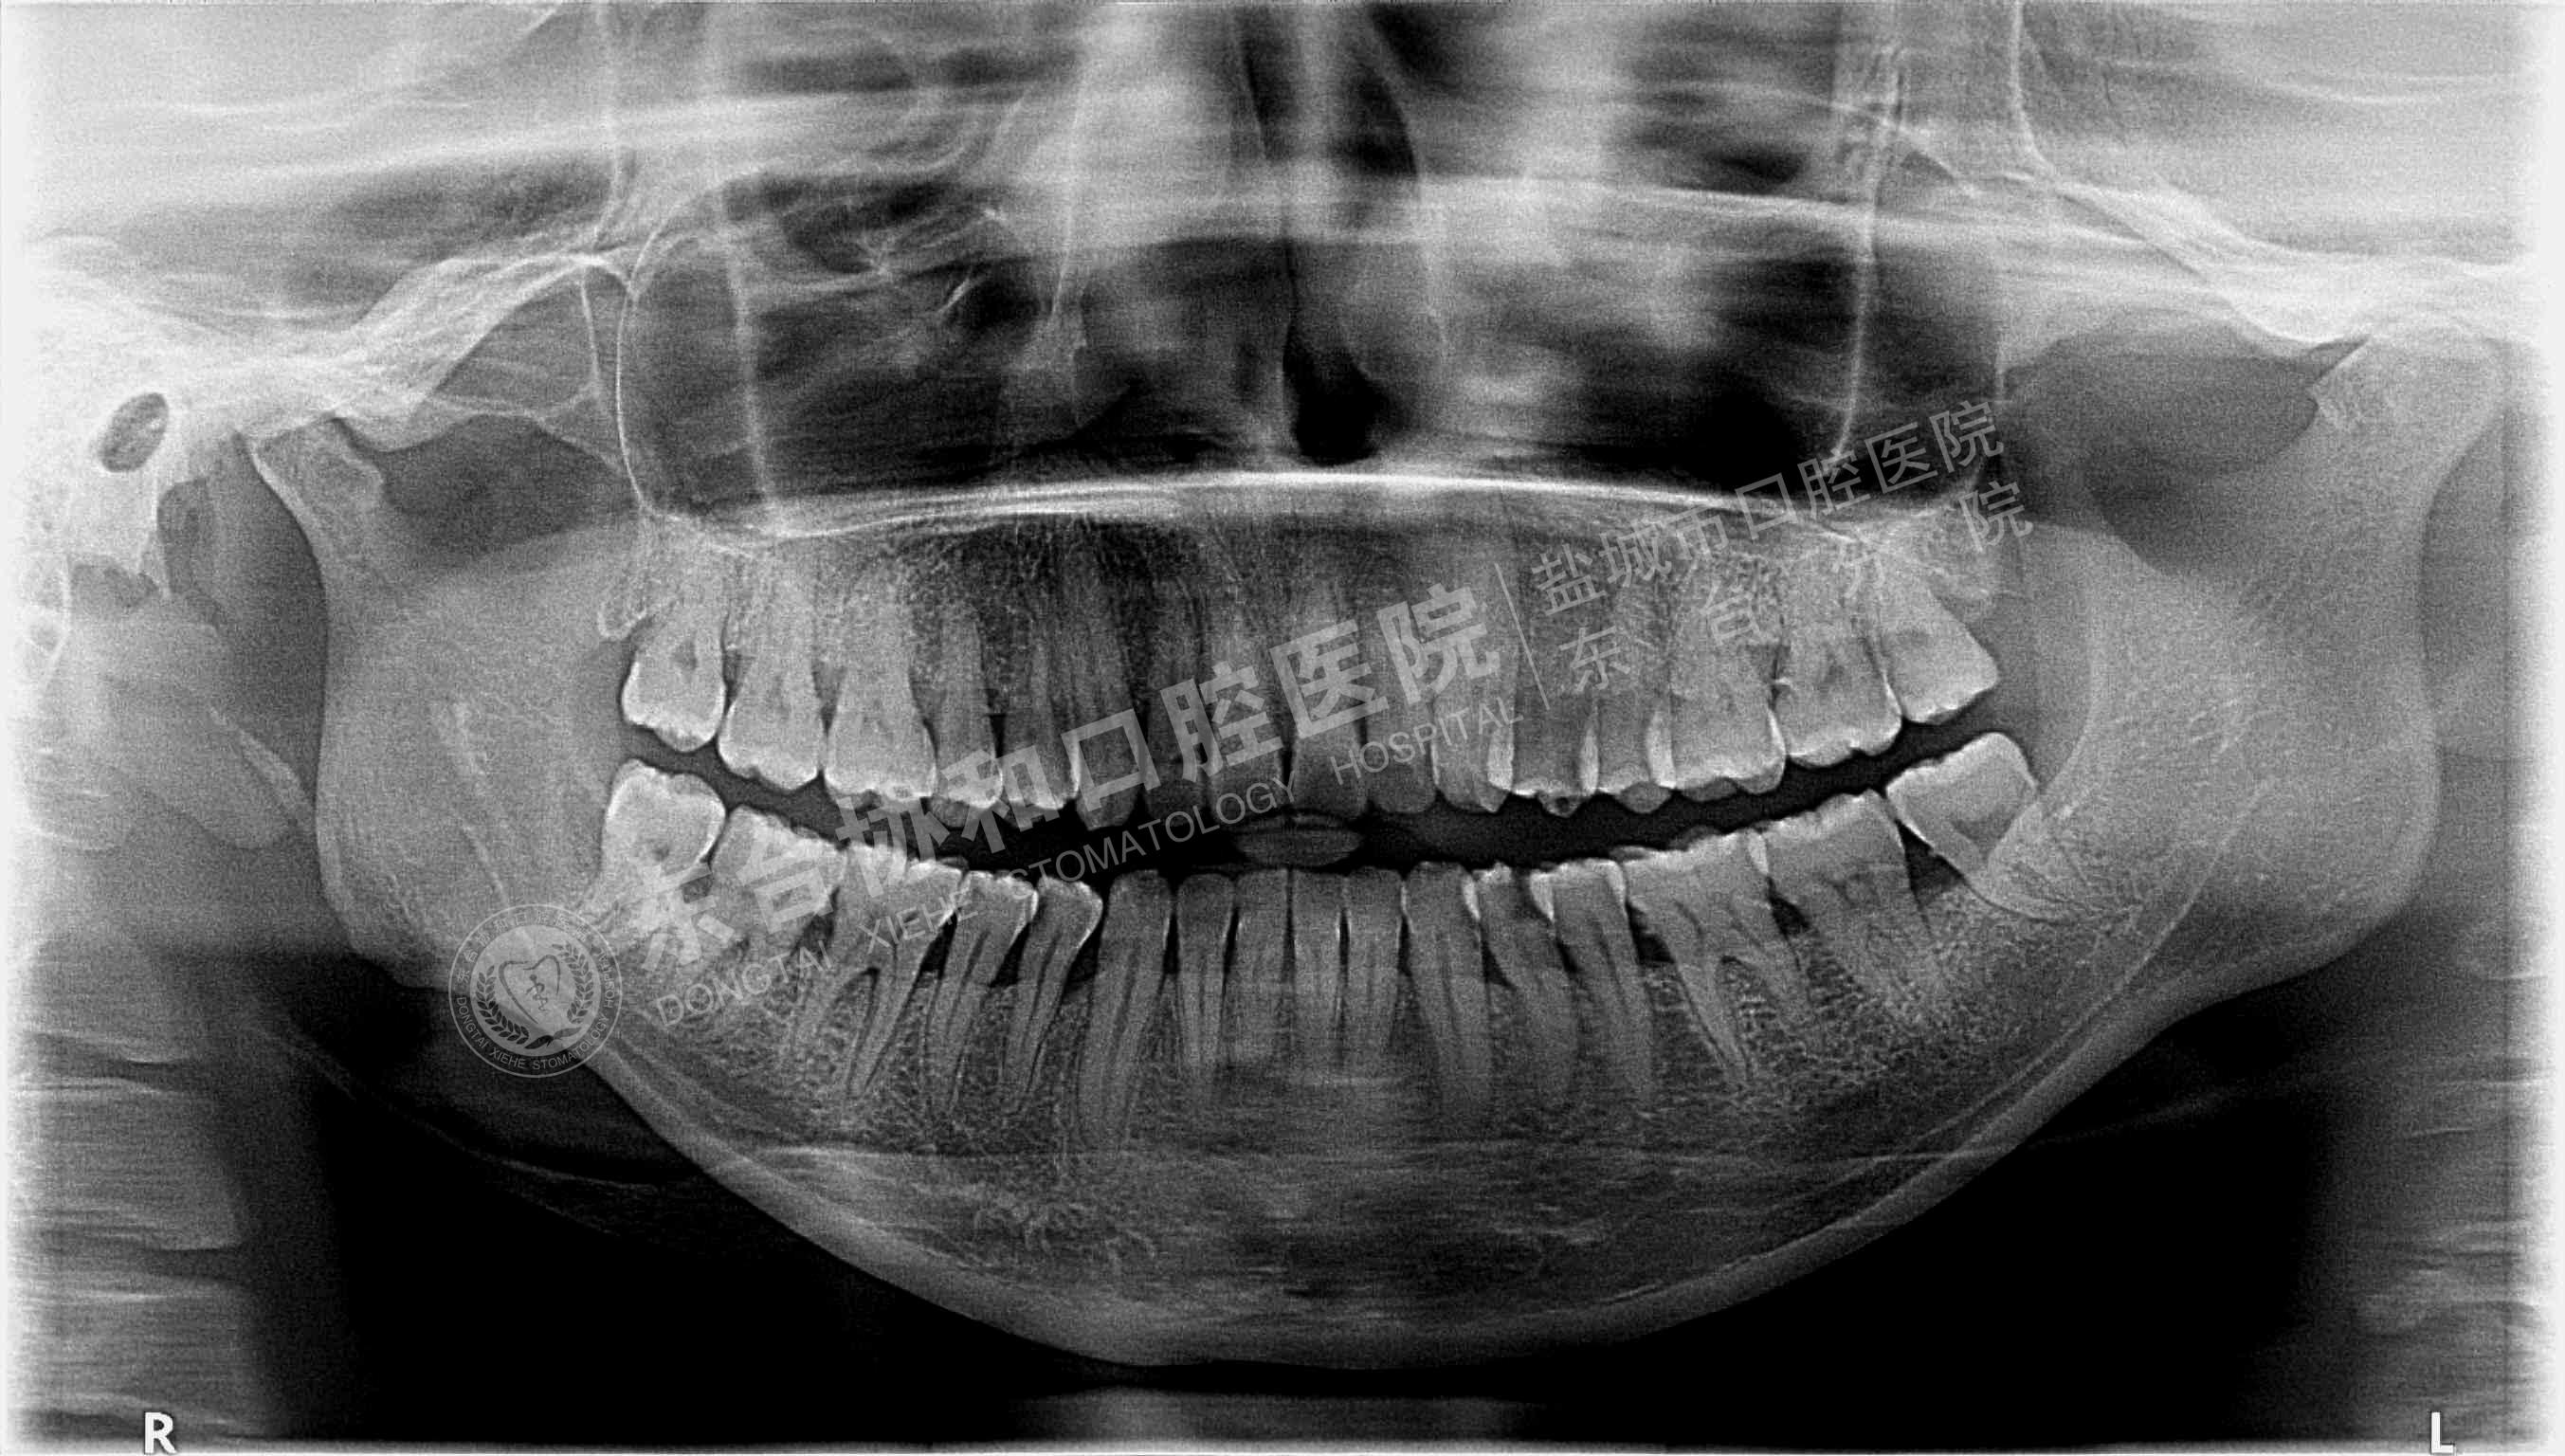

很多患者都很排斥拍牙片,認(rèn)為醫(yī)院是為了多收錢(qián)才讓他們拍的,其實(shí)這是一個(gè)錯(cuò)誤的想法,拍牙片是口腔科常用重要的檢查手段,臨床檢查只能直觀判斷牙冠和牙齦部分的情況,而對(duì)于牙根,牙槽骨、牙周膜等情況則必須通過(guò)牙片檢查。牙齒在牙片上顯示出白色阻射影像,其中牙釉質(zhì)阻射強(qiáng),牙本質(zhì)和牙骨質(zhì)阻射低于牙釉質(zhì),牙髓腔呈灰黑色影像,根管口至根尖孔呈逐漸變細(xì)的影像。

通過(guò)牙片除了了解牙齒的病變情況,還可以了解牙槽骨內(nèi)是否有埋伏牙、多生牙、牙源性腫瘤和囊腫等,依據(jù)牙片綜合分析可以提高牙齒診斷調(diào)節(jié)的準(zhǔn)確性和。

不同病種拍牙片的意義1、頜面部外傷:了解牙齒是否折裂、牙槽骨骨折程度和范圍。

2、牙齒硬組織病變:牙頸部牙根部齲齒、鄰面齲、確定齲壞的程度和齲壞的范圍;齲壞深度與牙髓腔的關(guān)系;了解齲壞與牙髓腔的距離;了解髓腔的變化情況和根尖周情況。

3、牙髓病變:牙片幫助檢查牙髓是否被吸收。

4、根尖周炎癥:了解病牙根管情況:如根管數(shù)目、粗細(xì)、彎曲度以及有無(wú)鈣化、有無(wú)內(nèi)吸收等情況;根管調(diào)節(jié)后的充填情況。如果牙齒需要做根管調(diào)節(jié),則牙片需要拍三張以上。調(diào)節(jié)前拍片是用來(lái)判斷是否根尖炎或者是囊腫的大小、范圍等,判斷是否需要根管調(diào)節(jié);根管預(yù)備術(shù)中片,檢查根管調(diào)節(jié)的長(zhǎng)度,調(diào)節(jié)后評(píng)價(jià)根管調(diào)節(jié)成功與否。

5、牙周炎癥:顯示牙槽骨吸收范圍和破壞程度。

6、用于阻生牙、埋伏牙及替換牙的檢查和調(diào)節(jié)。

7、牙片來(lái)確定乳牙和恒牙的相對(duì)位置,用來(lái)幫助醫(yī)生診斷乳牙是否能自行脫落還是需要拔除。

8、牙齒矯正:拍攝口腔全景片和頭顱側(cè)位片,以檢查骨骼和牙齒的發(fā)育情況。

9、拔牙檢查牙根情況以及牙槽骨破壞程度,牙齒是否拔除干凈以及牙槽窩形態(tài)是否完好。

10、種植牙拍牙片顯示牙槽骨的健康狀況、高度、密度,是否適合于種植牙;種植體的成活情況。